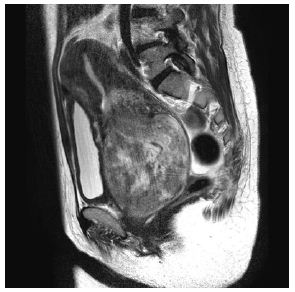

A 50 year old woman, G3P3, had a 1-year history of intermittent vaginal bleeding and progressive anemia. Physical examination revealed an ellipse of semi-solid; smooth surfaced mass occupying the vaginal cavity and hemoglobin level was remarkably decreasing (1.2 g/dl). Transfusion therapy was started immediately and intravenous iron prescribed to optimize her hemodynamic state. MRI detected a vaginal heterogenous mass 10x15x11cm, with regular edges and a vascular pedicle (Figure 1a). The mass seemed to dilate cervix up to the uterine fundus. Consideration of the inability to reach the pedicle through the vagina and the heavy vascularization of the fibroid led to the surgical approach through abdominal. The patient was put off UAE to reduce the blood supply, within 24 hours, with a surgical excision of 70% of the fibroid vaginally and subsequent simple abdominal hysterectomy and bilateral salpingo-oophorectomy.

Figure 1a: Large pedunculated submucosal fibroid prolapsed into the vagina in 50-year-old women. Sagittal T2-weighted MR images show a solid mass occupying vaginal cavity (arrow head) and atrophic normalappearing uterus was visible (arrow). Pathologically, the tumor was diagnosed as a leiomyoma.